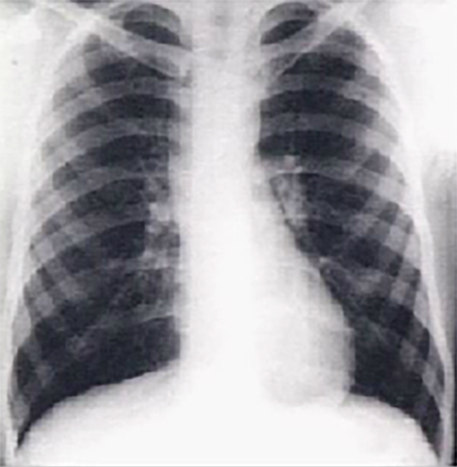

This PA chest X ray shows a dilated ascending aorta. It demonstrated dilatation of the ascending portion of the aorta, as evidenced by a prominent bulge in the right mediastinal shadow. Note that the heart size is normal, as reflected by a cardiothoracic ratio less than fifty percent.